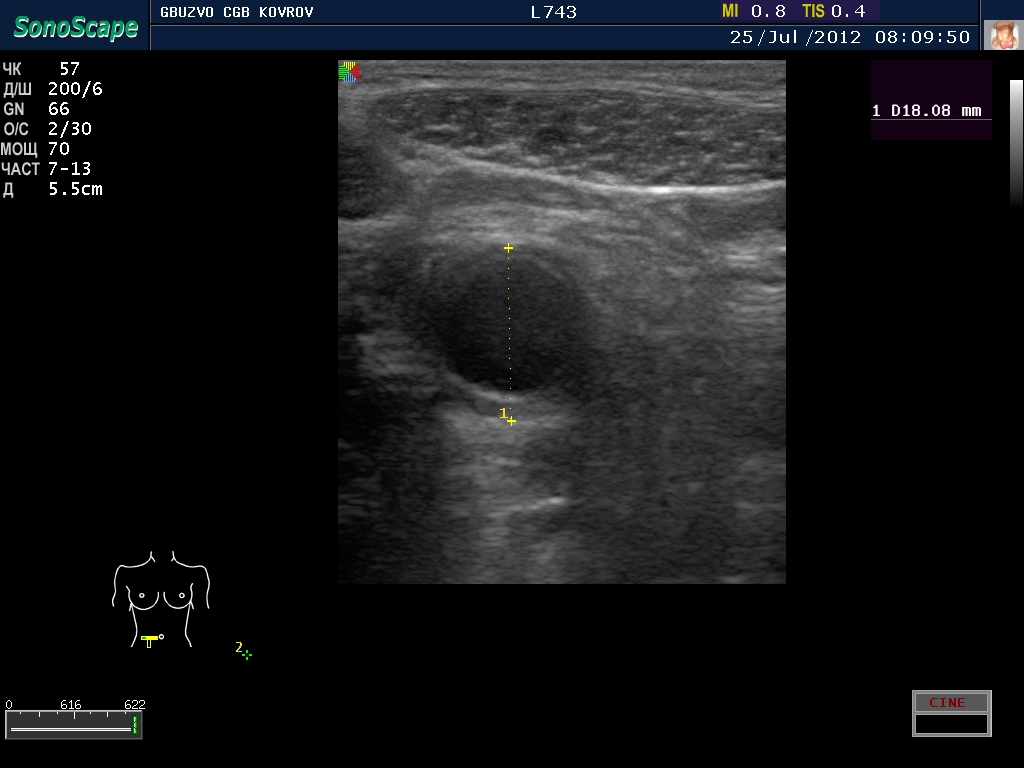

Пациент с жалобами на боли в животе...

полечили два дня в гастроэнтерологии...состояние ухудшилось, узи контроль----->

поподробнее? :shock: бодимаркер находится в правой подвсздошной области, я бы подумал про аппендикс 8-)